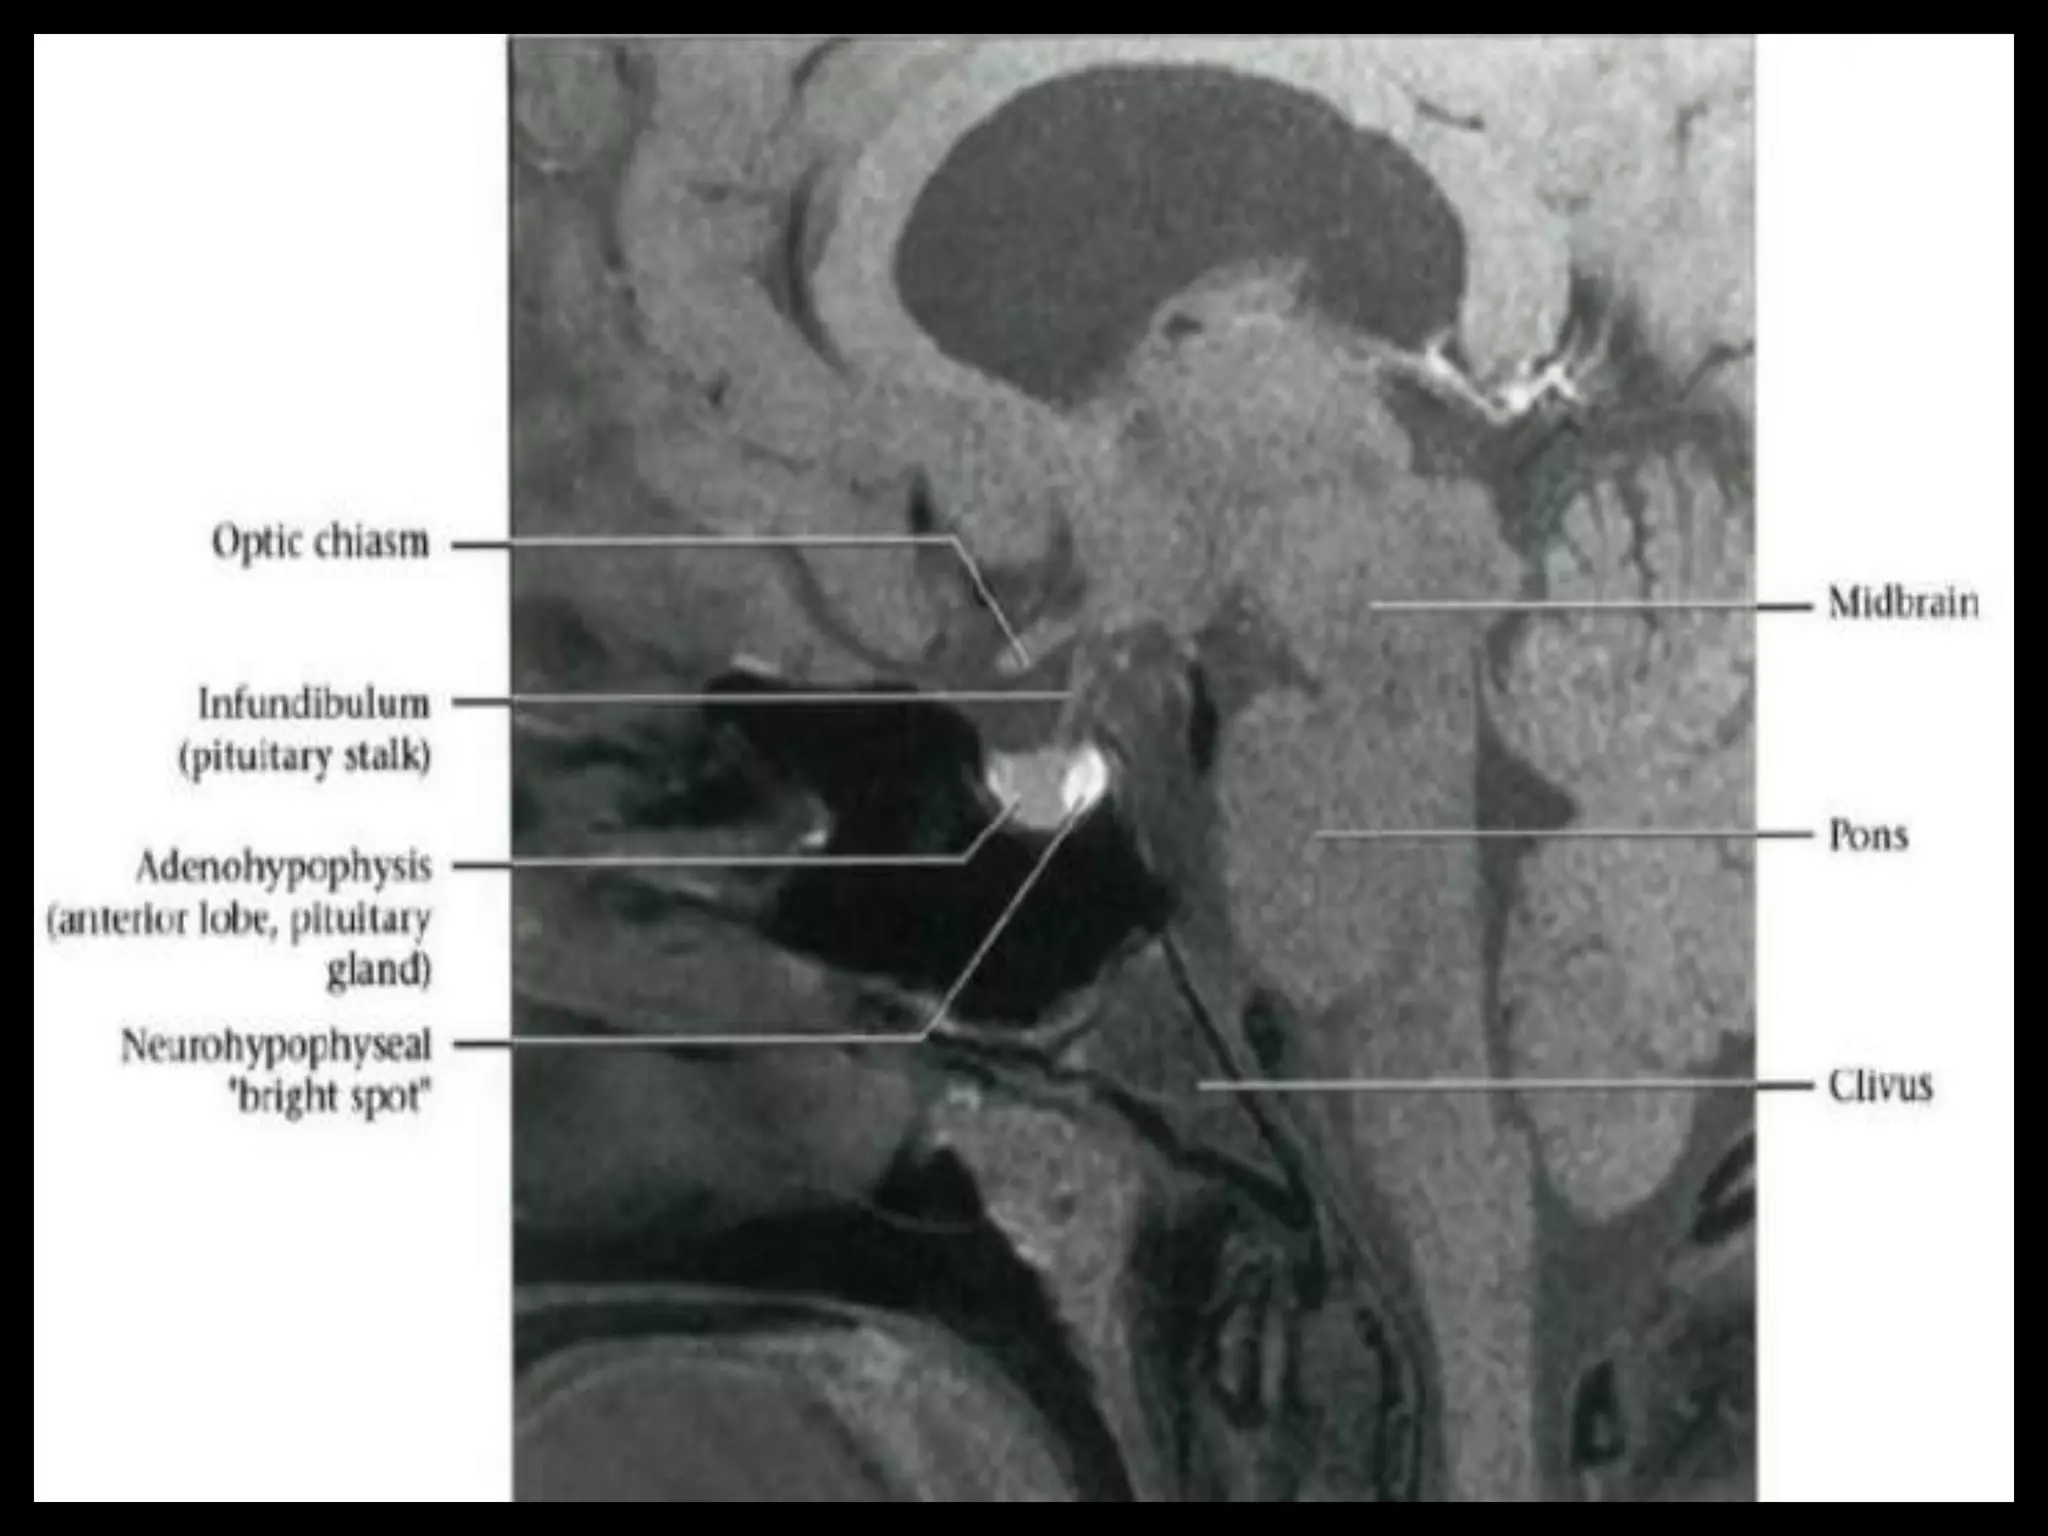

Pituitary Fossa.

Sectional Anatomy: NormalAxial CT and MRI Anatomy. On CT and MR scans, the brain has been briefly viewed in infratentorial and supratentorial sections, as described below. CT scans are performed with a 15- to 20-degree angulation to the canthomeatal line at 8-mm increments. MRI scans are generally obtained parallel to the AC-PC line in the axial plane with 6-mm slice thickness. Using the sagittal view, the coronal sections are acquired parallel to the brain stem, and the sagittal sections are obtained perpendicular to the axial section. On MRI studies, cranial nerves IX and X can be demonstrated at this level because they emerge from the postolivary sulcus. The posterior aspect of the cerebellar hemispheres is outlined by the inferior portion of the cisterna magna.

Suprasellar Cistern AndOptic Apparatus.